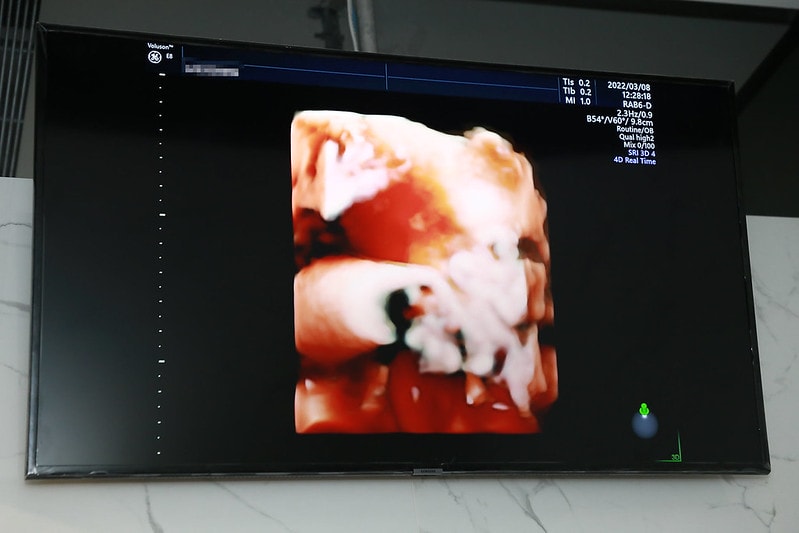

診所還有4D超音波

也可以把照片存起來

特別適合我這種很愛拍照的孕媽咪XD

產檢就是會直接照超音波~

然後醫生檢查寶寶的大小

跟說目前胎兒發展的狀況

還有比方說頭圍大小阿

胎位正不正之類的狀態